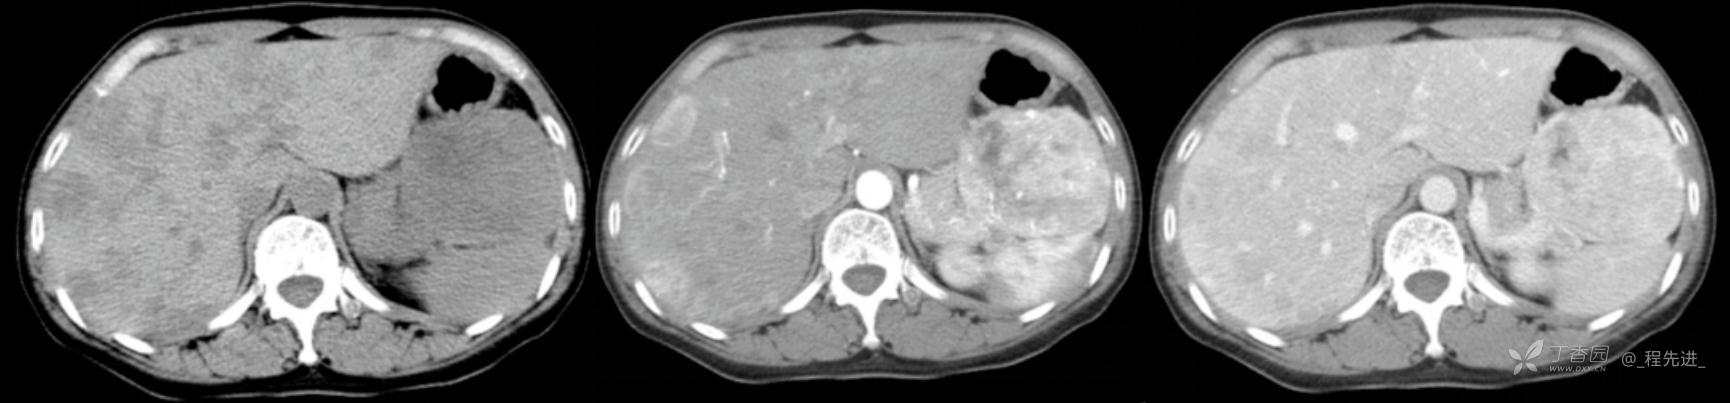

图像左边为平扫,中间的是动脉期,右边的是静脉期